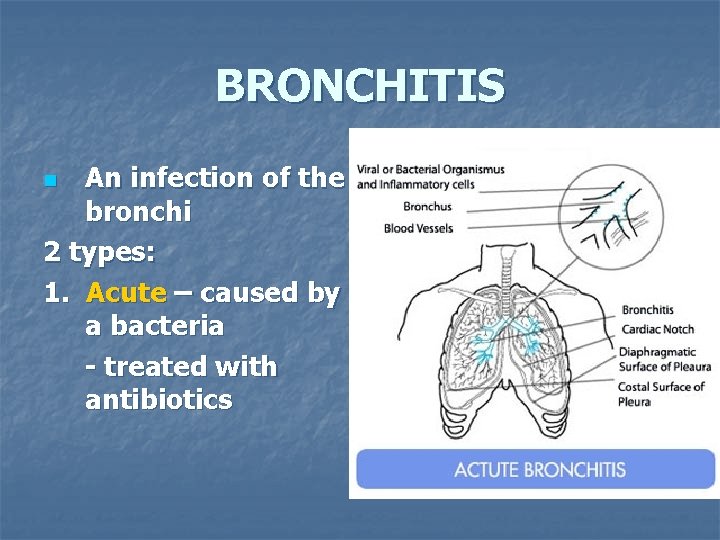

BRONCHITIS An infection of the bronchi 2 types: 1. Acute – caused by a bacteria - treated with antibiotics n